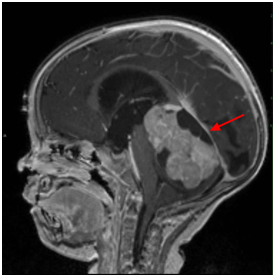

髓母细胞瘤是儿童中较常见的恶性脑肿瘤。根据定义,髓母细胞瘤发生在小脑中,小脑是位于头骨基部的脑部的一部分,位于脑干上方。小脑参与许多功能,包括协调自愿运动(例如,步行,细致运动技能)和调节平衡和姿势。髓母细胞瘤起源于大脑中原始的未发育细胞。大多数髓母细胞瘤发生在婴儿和儿童中。不太常见的是,这些肿瘤也可以在成人中发展。与髓母细胞瘤相关的症状包括早晨的头痛,随着白天的进行而好转,反复呕吐,行走困难和平衡。髓母细胞瘤可以扩散到中枢神经系统的其他区域。髓母细胞瘤的确切原因尚不清楚。髓母细胞瘤能治愈吗?手术是当前优选方法。

髓母细胞瘤的症状通常是由于颅内压力增加(颅内压)引起的。髓母细胞瘤通常出现在颅底或其附近,称为后颅窝。后颅窝包含脑干和小脑。

髓母细胞瘤通常涉及充满液体的四腔(脑室)。大脑有四个腔,称为脑室,充满脑脊液(CSF)并通过通道连接,CSF通过这些通道循环。由于肿瘤常填充四脑室,因此CSF循环受阻,导致脑积水。脑积水是一种状态,其中大脑中过量脑脊液的积聚导致各种症状,包括反复的,经常严重的呕吐,嗜睡和头痛,这些症状经常在早晨发生并随着日子的进行而好转。其他症状可能包括烦躁,头部大小增加,肌肉麻痹(麻痹),有助于控制眼球运动(眼外肌)。